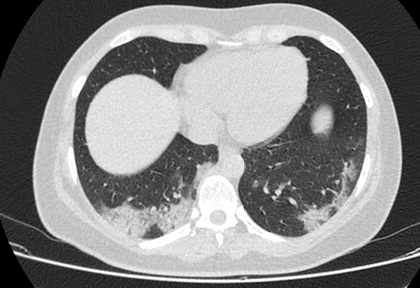

Routine clinical laboratory assays were performed in the hospital’s clinical laboratories. Clinical and laboratory information was extracted from the patients’ medical records. C reactive protein (CRP) in plasma was measured by immunoturbidimetry (Beckman Coulter, Krefeld, Germany). Interleukin-6 (IL-6) levels in plasma were measured by electrochemiluminescence (Siemens Medical Solutions Diagnostics, Siemens Healthcare, Erlangen, Germany). CT scans were read by experienced radiologists who scored results by severity using the criteria shown in Figure 1.

Figure 1. Clinical assessment of pneumonia severity based on computed tomography (CT) scores.

Scoring method: Mild (CT-1)—no more than three ground-glass opacities of <3 cm maximum diameter. Moderate (CT-2)—more than three ground-glass opacities; less than 50% involvement by visual assessment. Medium-heavy (CT-3)—ground-glass opacities and pulmonary consolidation; 50-70% involvement by visual assessment. Severe (CT-4)—diffuse ground-glass opacities with or without consolidation; more than 75% involvement by visual assessment.